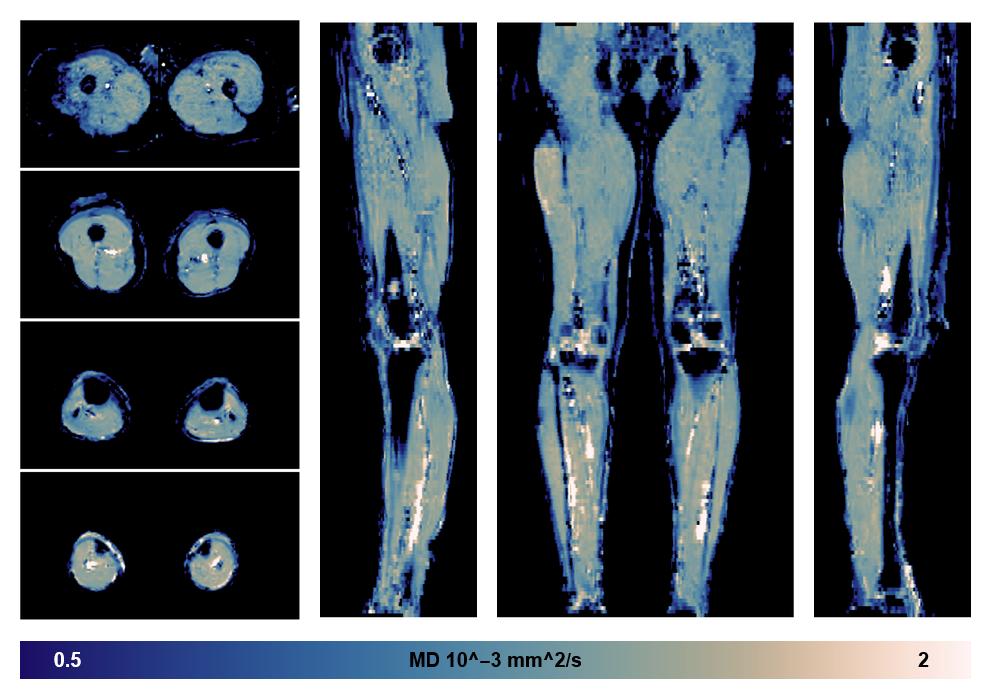

• Mean diffusivity

IVIM corrected whole leg muscle mean diffusivity obtained from diffusion tensor imaging.